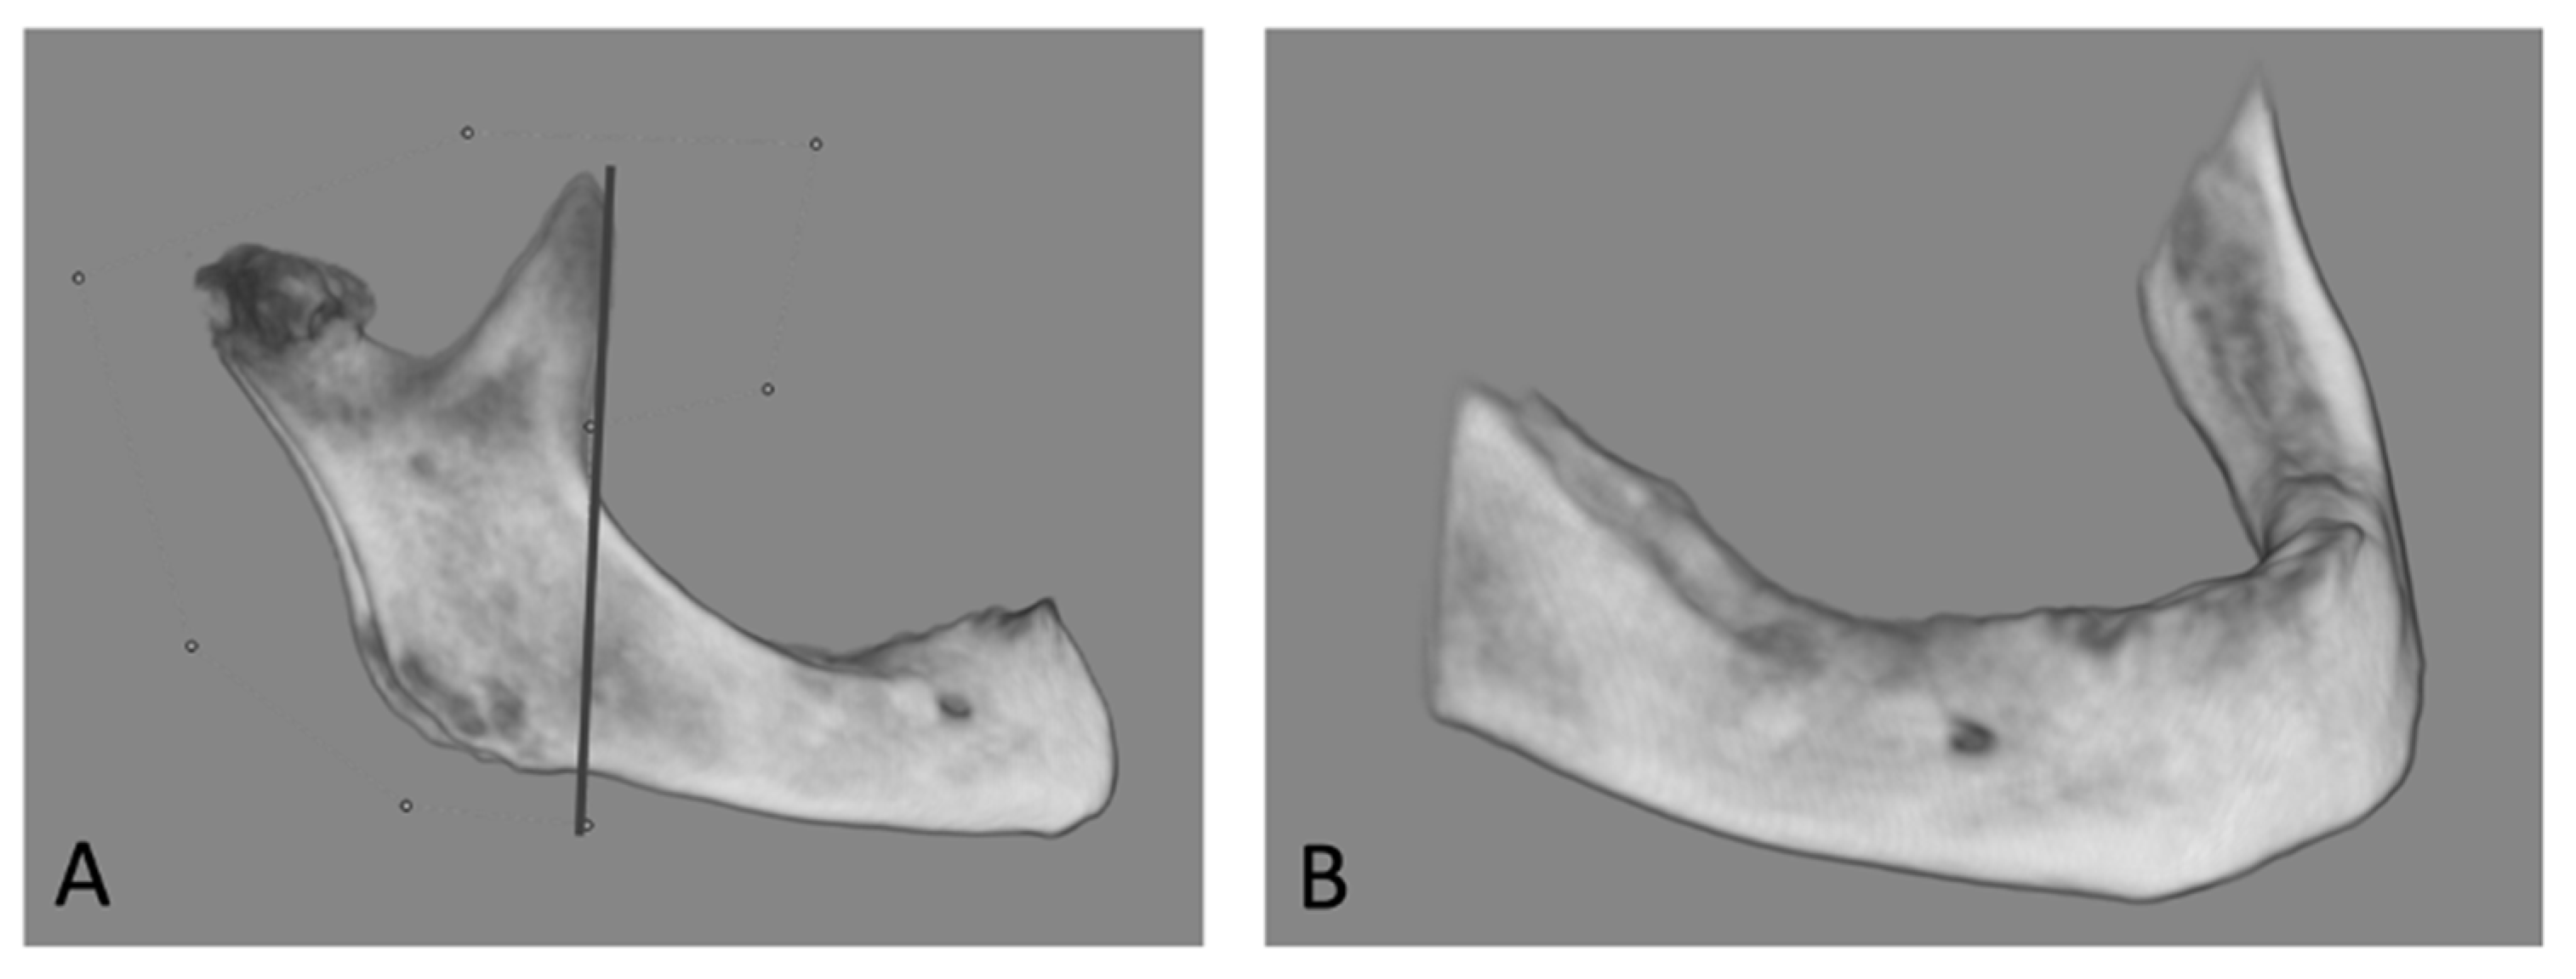

2.5. CBCT Measurements